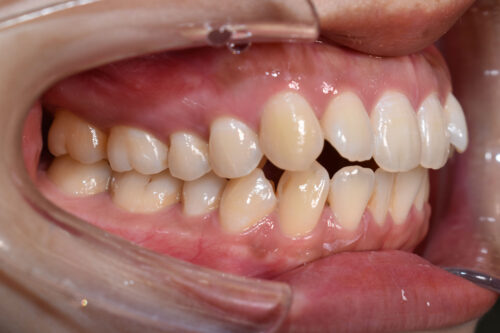

ワイヤー矯正治療11か月後です。

全額矯正治療 88万円、3~4週に一回来院

歯科矯正用アンカースクリュー(デュアル・トップオートスクリュー)上顎左右2本(25000円x1本分 提携医院にて)

ワイヤー期間 11か月, 17回来院

本症例のように

屋根のように 上下の歯が 唇側に傾斜しており

口元が出っ歯に見えるのを気になさる患者様も多くいらっしゃいます。

昔は 第一小臼歯を4本抜歯して 矯正治療をしましたが、

今は 歯科矯正用アンカースクリュー(デュアル・トップオートスクリュー)を利用する

ことで

歯を抜かなくても 歯列全体を後方へ移動することができるようになりました。